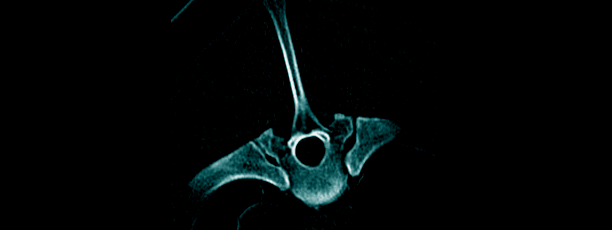

ΟΡΘΟΠΕΔΙΚΑ ΠΡΟΒΛΗΜΑΤΑ

Ορθοπεδικα προβληματα – Χρηση προηγμενης απεικονιστικης διαγνωστικης. ΑΠΑΙΤΕΙΤΑΙ: -Γνωστικη εξειδικευση και τεχνογνωσια ληψεων για τη δυνατοτητα ελεγχου ειδικων παθησεων και προσδιορισμο των αιτιων τους. -Χρησιμοποιουνται προγραμματα και πρωτοκολα ελεγχου και μετρησεων. -ΑΦΟΡΟΥΝ: Στον ελεγχο της ανατομιας και οστεοπαθολογιας. Στον ελεγχο των γωνιων ακρου,για προγνωση και διαγνωση ειδικων κατηγοριων παθησεων οπως π.χ.εξαρθρηματων επιγονατιδας. Συμβουλευτικη και βασικη …